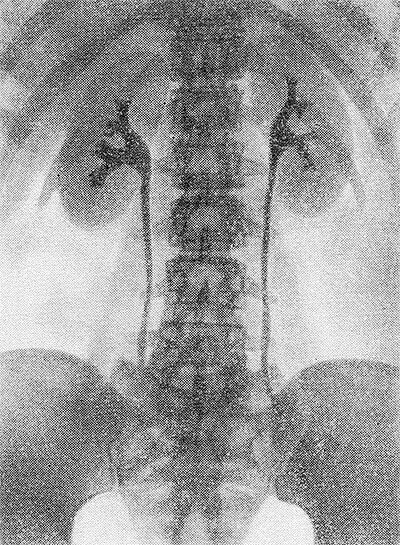

После урографии